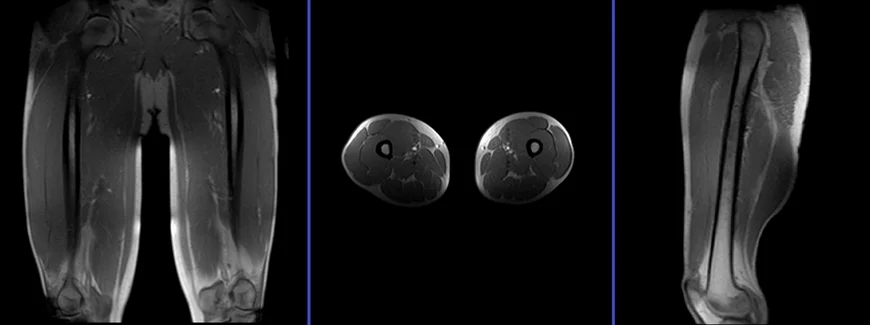

Thigh MRI is a non-invasive imaging technique that provides detailed visualization of the structures within the thigh, including muscles, bones, tendons, ligaments, blood vessels, and nerves. This powerful tool utilizes a strong magnetic field and radio waves to create cross-sectional images, offering a comprehensive view of the thigh's anatomy and any potential abnormalities.

The high-resolution images produced by thigh MRI enable physicians to accurately diagnose and localize injuries, assess the extent of damage, and guide treatment decisions. It is a safe and effective method for evaluating both acute and chronic thigh conditions, providing valuable insights into the underlying causes of pain, swelling, and limited mobility.

Thigh MRI is a comprehensive diagnostic tool, offering detailed insights into a wide spectrum of conditions affecting the thigh region. Beyond its proficiency in identifying marrow abnormalities such as avascular necrosis, marrow edema syndromes, and stress fractures, MRI excels in visualizing soft tissue structures, making it invaluable for diagnosing muscle strains, tears, tendonitis, and tendonopathy. These conditions are particularly prevalent in athletes and active individuals, where the demands placed on the thigh muscles and tendons can lead to overuse injuries or acute trauma.